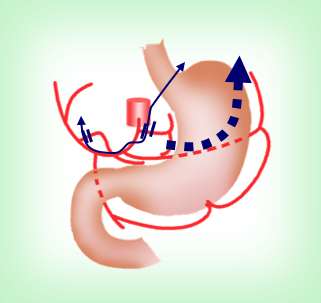

左のような位置の小さなきずから手術を行います。

きずの位置は手術する病院、医者によってさまざまですが、当院では左のようなきずで行います。

みぞおちのきずは、切った胃を取り出したり、腸と腸をつないだりする時に4cmほどに広げます。

- ● 12mm カメラを入れるきず

- ● 5mm 主に術者が使う器具を入れるきず

- ● 12mm 主に術者が使う器具を入れるきず

- ● 5mm 主に助手の使う器具を入れます

- ━ 胃の取り出し、胃と腸・腸と腸の縫い合わせの時に使います